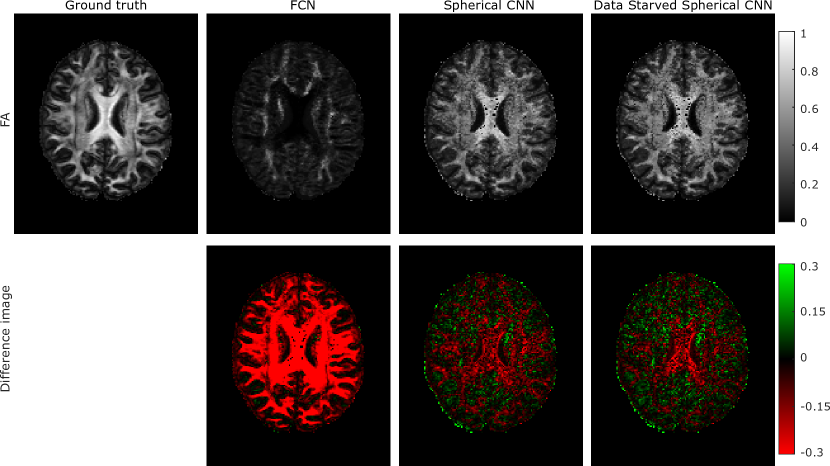

Figure 4: Comparison between the FCN model and the S-CNN model at estimating the FA when trained only with microstrucure oriented along the anterior-posterior axis. These are also compared against a training data starved S-CNN. We see that spherical CNN outperforms FCN as the noise is greatly reduced and less structured. Data starved S-CNN performs similarly well to the S-CNN trained using the full dataset.

5.2 For Experiment 2

The results of experiment 2 are shown in figures 3, 4 and 5. Figure 4 qualitatively shows the effect of estimating the full brain volume using networks trained only on tissue microstructure aligned with the anterior-posterior axis. The FCN model consistently underestimates FA in regions where the underlying tissue microstructure does not align with anterior-posterior direction (e.g. the corpus callosum which consists of left-right white matter tracts). In contrast, the S-CNN models accurately estimate FA independently of the primary fibre direction, and the error is far less structured than the FCN’s.

In figures 3 and 4 another advantage of rotational equivariance is shown. Performance of the S-CNN network is not greatly changed when only a tenth of the training dataset is used. This is shown in the maps of FA estimated by the data starved S-CNN model in figure 4 and the RMSE over the 12 testing subjects shown in figure 3. The robustness to a lack of training data is due to S-CNNs being rotationally equivariant. Therefore, during training only a diverse distribution of the microstructure shape is required and not their orientations as well. This property of S-CNNs is a real benefit as it reduces the number of training datapoints required for good estimation at inference stage and, when simulating training data, allows for denser sampling of the shape parameters as SO(3) need not be sampled.